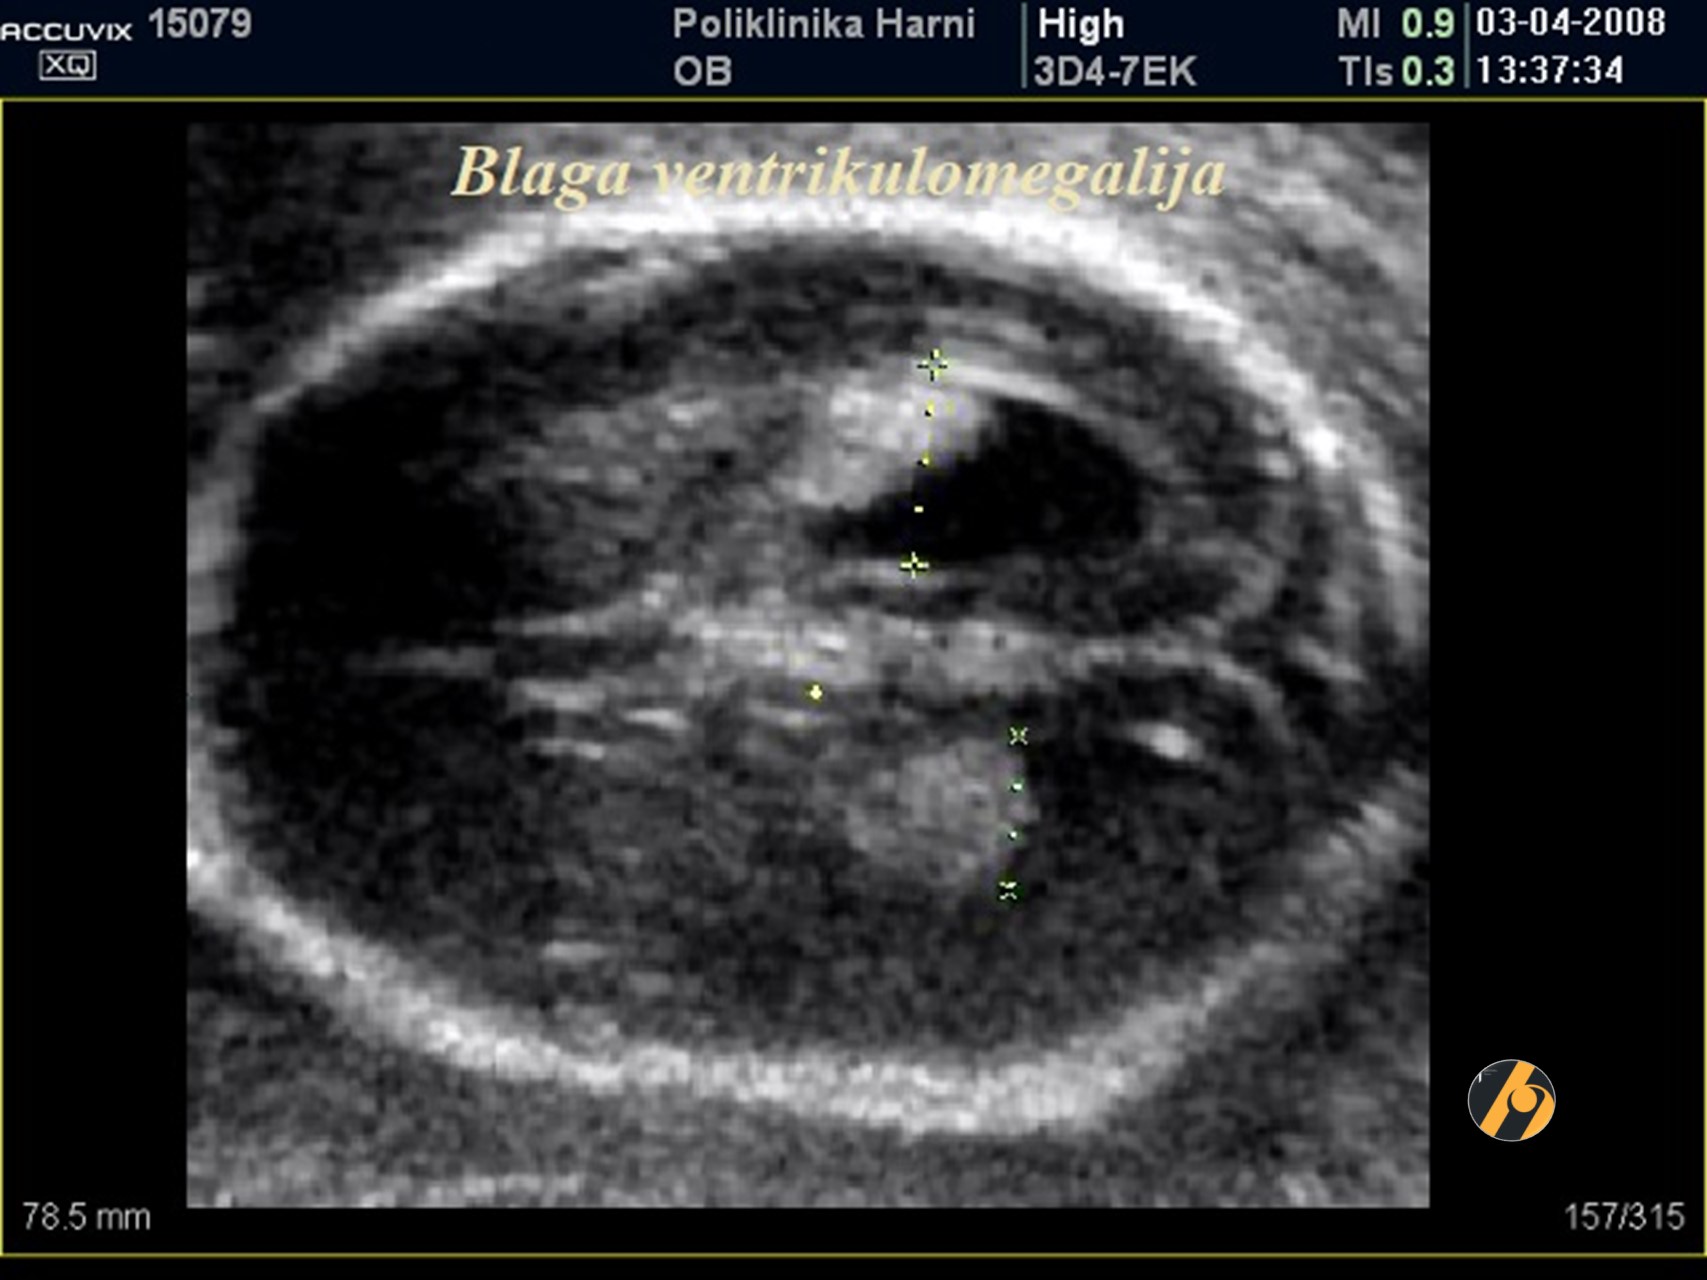

Ventrikulomegalija, definirana promjerom lateralnog ventrikula od 10 mm ili više, se nalazi u 1% trudnoća prilikom pregleda s 20.-22. tjedna.

Može biti posljedica kromosomskih i genetskih poremećaja, intrauterinog krvarenja ili urođene infekcije, iako mnogi slučajevi nemaju jasnu etiologiju. U većini slučajeva dijagnoza se postavlja u drugom tromjesečju. U prvom tromjesečju se dijagnoza može postaviti ako su koroidni pleksusi, koji obično ispunjavaju lateralne ventrikule, okruženi tekućinom.